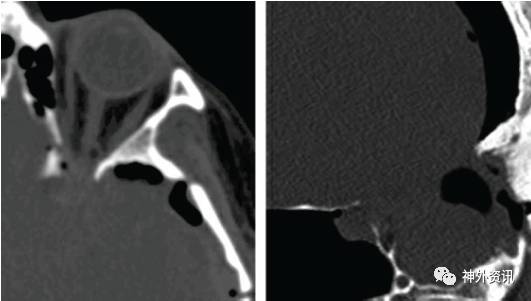

脑膜瘤可导致眶顶和蝶骨翼外侧部的骨质增生,术前影像学需评估这一情况。对这一类型脑膜瘤行眶颧开颅时,眶顶的切开须在直视下完成。由于眶顶骨质异常增厚,可出现难以控制的眶顶、眶缘骨折,甚至可累及视神经管而导致视神经损伤。当骨折累及蝶窦和筛窦时,还可出现术后脑脊液漏。

图3:须避免在未完全离断骨性连接、且未直视眶顶或蝶骨翼外侧部的情况下,盲目地掀起眶颧或翼点骨瓣。强行折断异常增生的蝶骨翼外侧部,可导致骨折线意外累及视神经管(左图)或筛窦(右图),出现相应的视神经损伤和术后脑脊液漏。